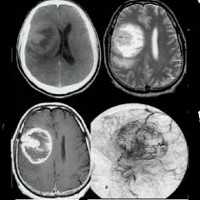

Постнатальный рост и регресс опухоли.

(А) У этого мальчика в трехмесячном возрасте при нормальной остроте зрения, но наличии множественных пятен типа «кофе с молоком» при МРТ не выявлено патологии хиазмы и зрительных путей.

(Б) Однако, через два года при МРТ обнаружен рост крупного контрастного образования в пределах границ хиазмы.

Также выявлено двустороннее поражение зрительных нервов, на некоторых томограммах распространяющееся дистальнее верхушки глазницы.

Тем не менее, острота зрения обоих глаз оставалась 20/20, относительный афферентный зрачковый дефект отсутствовал, несмотря на признаки атрофии диска зрительного нерва на левом глазу.

(В) Еще через два года на МРТ отмечается выраженное уменьшение размера опухоли, фактически без усиления контрастности. Острота зрения обоих глаз оставалась 20/20, ребенок оставался здоровым и бодрым. Спонтанный регресс глиомы зрительного нерва у 14-летней девочки.

(А) При МРТ выявляется веретенообразное утолщение левого зрительного нерва, дающее гиперинтенсивный и гомогенный сигнал, тянущееся от глазного яблока до хиазмы,

с изгибом зрительного нерва книзу, что создает впечатление его дефекта. Имеется левосторонний экзофтальм и расширение левого канала зрительного нерва.

(Б) При МРТ выявляется значительное увеличение внутриглазничной части левого зрительного нерва, с выраженным гомогенным усилением сигнала.

(В) МРТ через один год. Определяется уменьшение в размерах опухоли зрительного нерва по всей ее длине, сопровождающееся уменьшением интенсивности сигнала. Левосторонний экзофтальм разрешился.

(Г) На МРТ видно явное уменьшение диаметра зрительного нерва и лишь остаточное усиление сигнала в центральной зоне.

Этой девочке планировалось проведение лучевой терапии, но за неделю до начала лечения у нее было выявлено улучшение зрения.

Запланированные сеансы лучевой терапии были отменены, поскольку в течение года острота зрения улучшилась от счета пальцев с 4 футов до 20/15.

Если бы начало курса лучевой терапии было запланировано на неделю раньше, улучшения были бы ошибочно отнесены на счет эффектов проводимого лечения (пациентка Johns Hopkins Hospital).

Казуистические наблюдения уменьшения объема опухоли после лучевой или химиотерапии, особенно через длительное время после окончания терапии, вероятно, являлись следствием феномена спонтанного регресса.